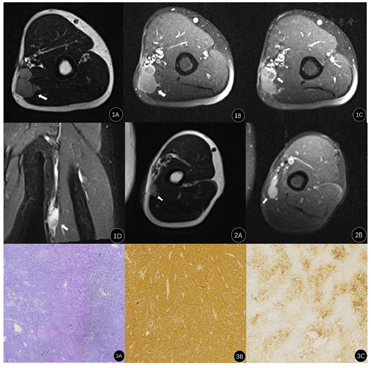

辅助检查:左上臂MRI提示:左侧上臂中段内侧皮下可见不规则长T1、长T2信号结节影,呈分叶状,PD抑脂高信号,与邻近血管、肱三头肌内侧头分界不清,大小约2.6cm×2.6cm。增强扫描病灶呈不均匀明显强化,其内可见低强化区(图1A,图1B,图1C,图1D)。术后3月左上臂MRI提示:左上臂中段内侧皮下可见类圆形稍长T1、长T2信号结节影,PD抑脂高信号,边界清,与邻近血管、肱三头肌内侧头分界清,大小约2.3cm×1.6cm(图2A,图2B)。余肱骨上臂肌肉内未见异常信号影。胸部CT平扫+增强未见明显异常。肝功:乙肝病毒表面抗体196.73(0~0.06IU/ml),乙肝病毒e抗体0.01(1~9999 S/CO),乙肝病毒核心抗体11.35(0~1 S/CO)。

患者8个月前左上臂发现一肿物,质软,无疼痛,不伴有关节红肿,未行特殊处理,近2个月发现肿物逐渐增大,活动过多后肿物出现疼痛。经MR检查诊断为软组织恶性肿瘤,入院行"左上臂肿物切除术",术中于肱二头肌及肱三头肌相邻部探及一类圆形肿物,质硬,表面不光整,大小约3cm×2.5cm,压迫肌肉,侵及深筋膜并与周围组织粘连明显。于正常组织内仔细分离后取部分肿瘤组织送检,术中快速冰冻病理检查结果:送检组织考虑恶性神经瘤。将肿瘤完全切除,并切除肿瘤周围1.5cm-2.0cm组织,术后病理及免疫组织化学诊断为左上臂软组织透明细胞肉瘤(图3A,图3B,图3C)。术后行吡柔比星、异环磷酰胺化疗方案,给予止吐、护肝保肾、升白细胞等抗化疗副反应药物治疗。3个月后随访患者又发现左上臂肿物,再次入院行"左上臂肿物切除术",并扩大范围切除肿瘤周围2cm-3cm组织,术后病理为软组织透明细胞肉瘤,考虑复发。术后更改化疗方案为阿霉素、异环磷酰胺化疗方案,并给予美司钠静点预防异环磷酰胺泌尿道毒性,盐酸阿扎司琼预防放射治疗,细胞毒性药物化疗引起的恶心呕吐。